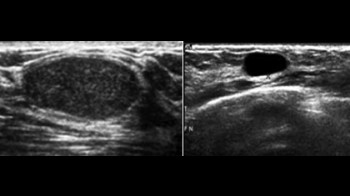

• Mamografiju i/ili ultrazvuk dojki

Šta je mamografija?

Mamografija je snimanje grudi sa niskom dozom rtg zracenja u cilju ranog otkrivanja karcinoma dojke koji je kod zena prvi po ucestalosti medju karcinomima. Preporucuje se uraditi je jednom godišnje, iza 40-te godine zivota, a ultrazvuk dojki do 40-te godine. Pregled takodjer treba uraditi ako osjetite tvrdo tkivo ili žlijezdu u grudima, iscjedak iz bradavice ili ako imate pozitivnu porodicnu anamnezu karcinoma dojke.

U 5-15% mamografskih snimaka naći ce se promjena koja zahtijeva dodatni pregled, kao ultrazvuk grudi, biopsiju ili kontrolnu mamografiju.